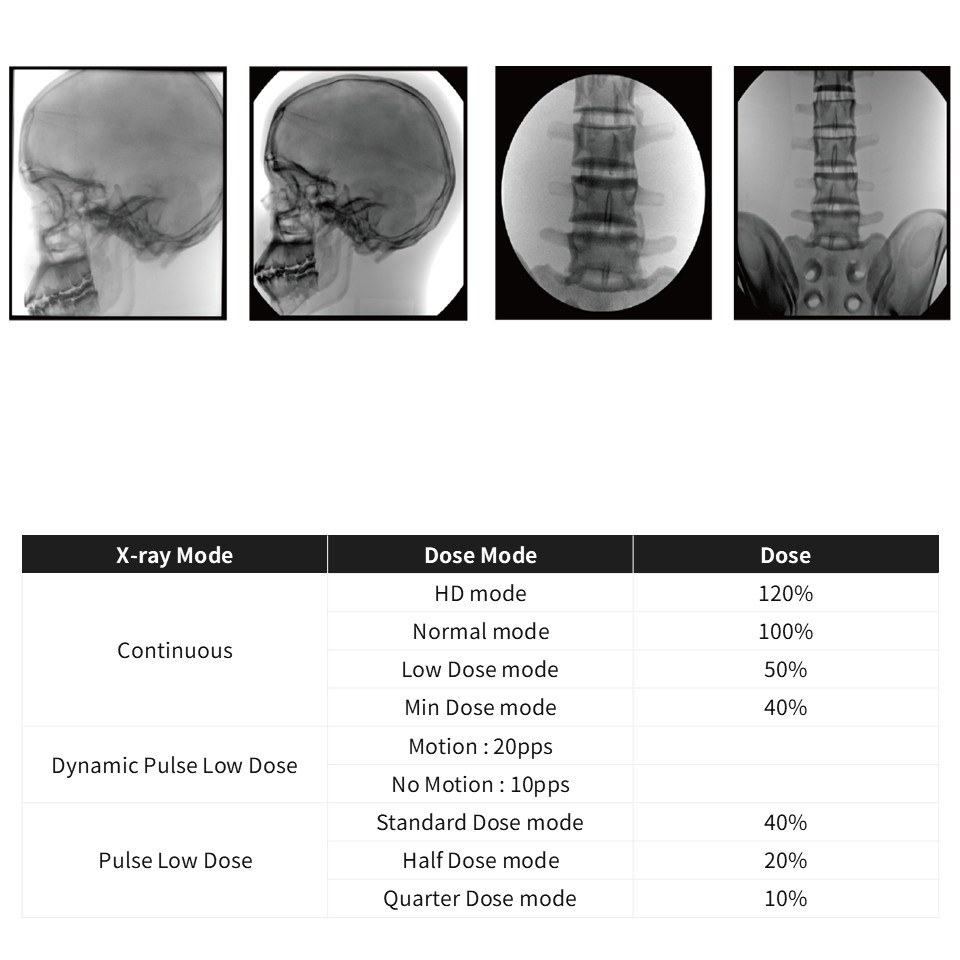

설치사례